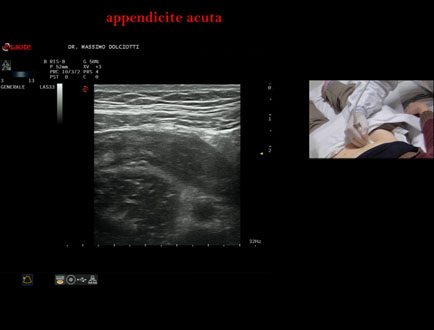

Data inserimento: 20/02/2026

Ecografia del: 13/02/2026

Strumento: Esaote MyLab Eight

Sonda: Lineare Multifrequenza 4-15 MHz

Età Paziente: M 22 anni

Motivazione dell'esame: da un giorno dolori addominali in sede ileo-cecale.

Commento all'esame: le immagini ed il video documentano, in sede ileo-cecale, appendice di spessore aumentato (9 - 10 mm - V.N. inferiore a 6 mm) con incremento della vascolarizzazione. Gli elementi ecografici segnalati orientano per appendicite acuta.

Conclusioni: appendicite acuta (acute appendicitis).

In collaborazione: Dr.ssa Marica Manfredi - Ancona, Dr. Ilir Qose - Ancona

Presentazione: Dr. Massimo Dolciotti - Ancona